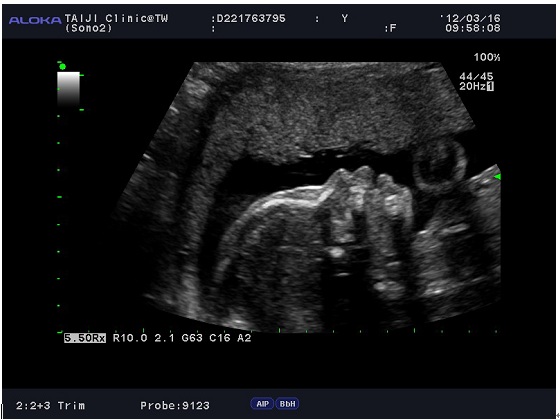

林醫生確認胎盤、羊水的狀況都很正常,

也就是基本上搭飛機不會有什麼太大問題,

所以幾個小時後,我們就開開心心的出發啦^___^